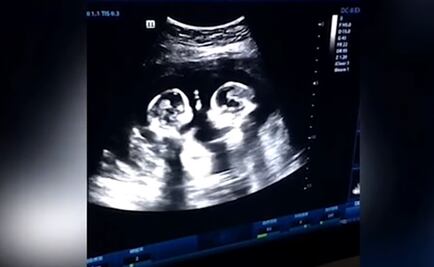

La Chica Badabun explicó que no había presentado a Eros Demian por seguridad